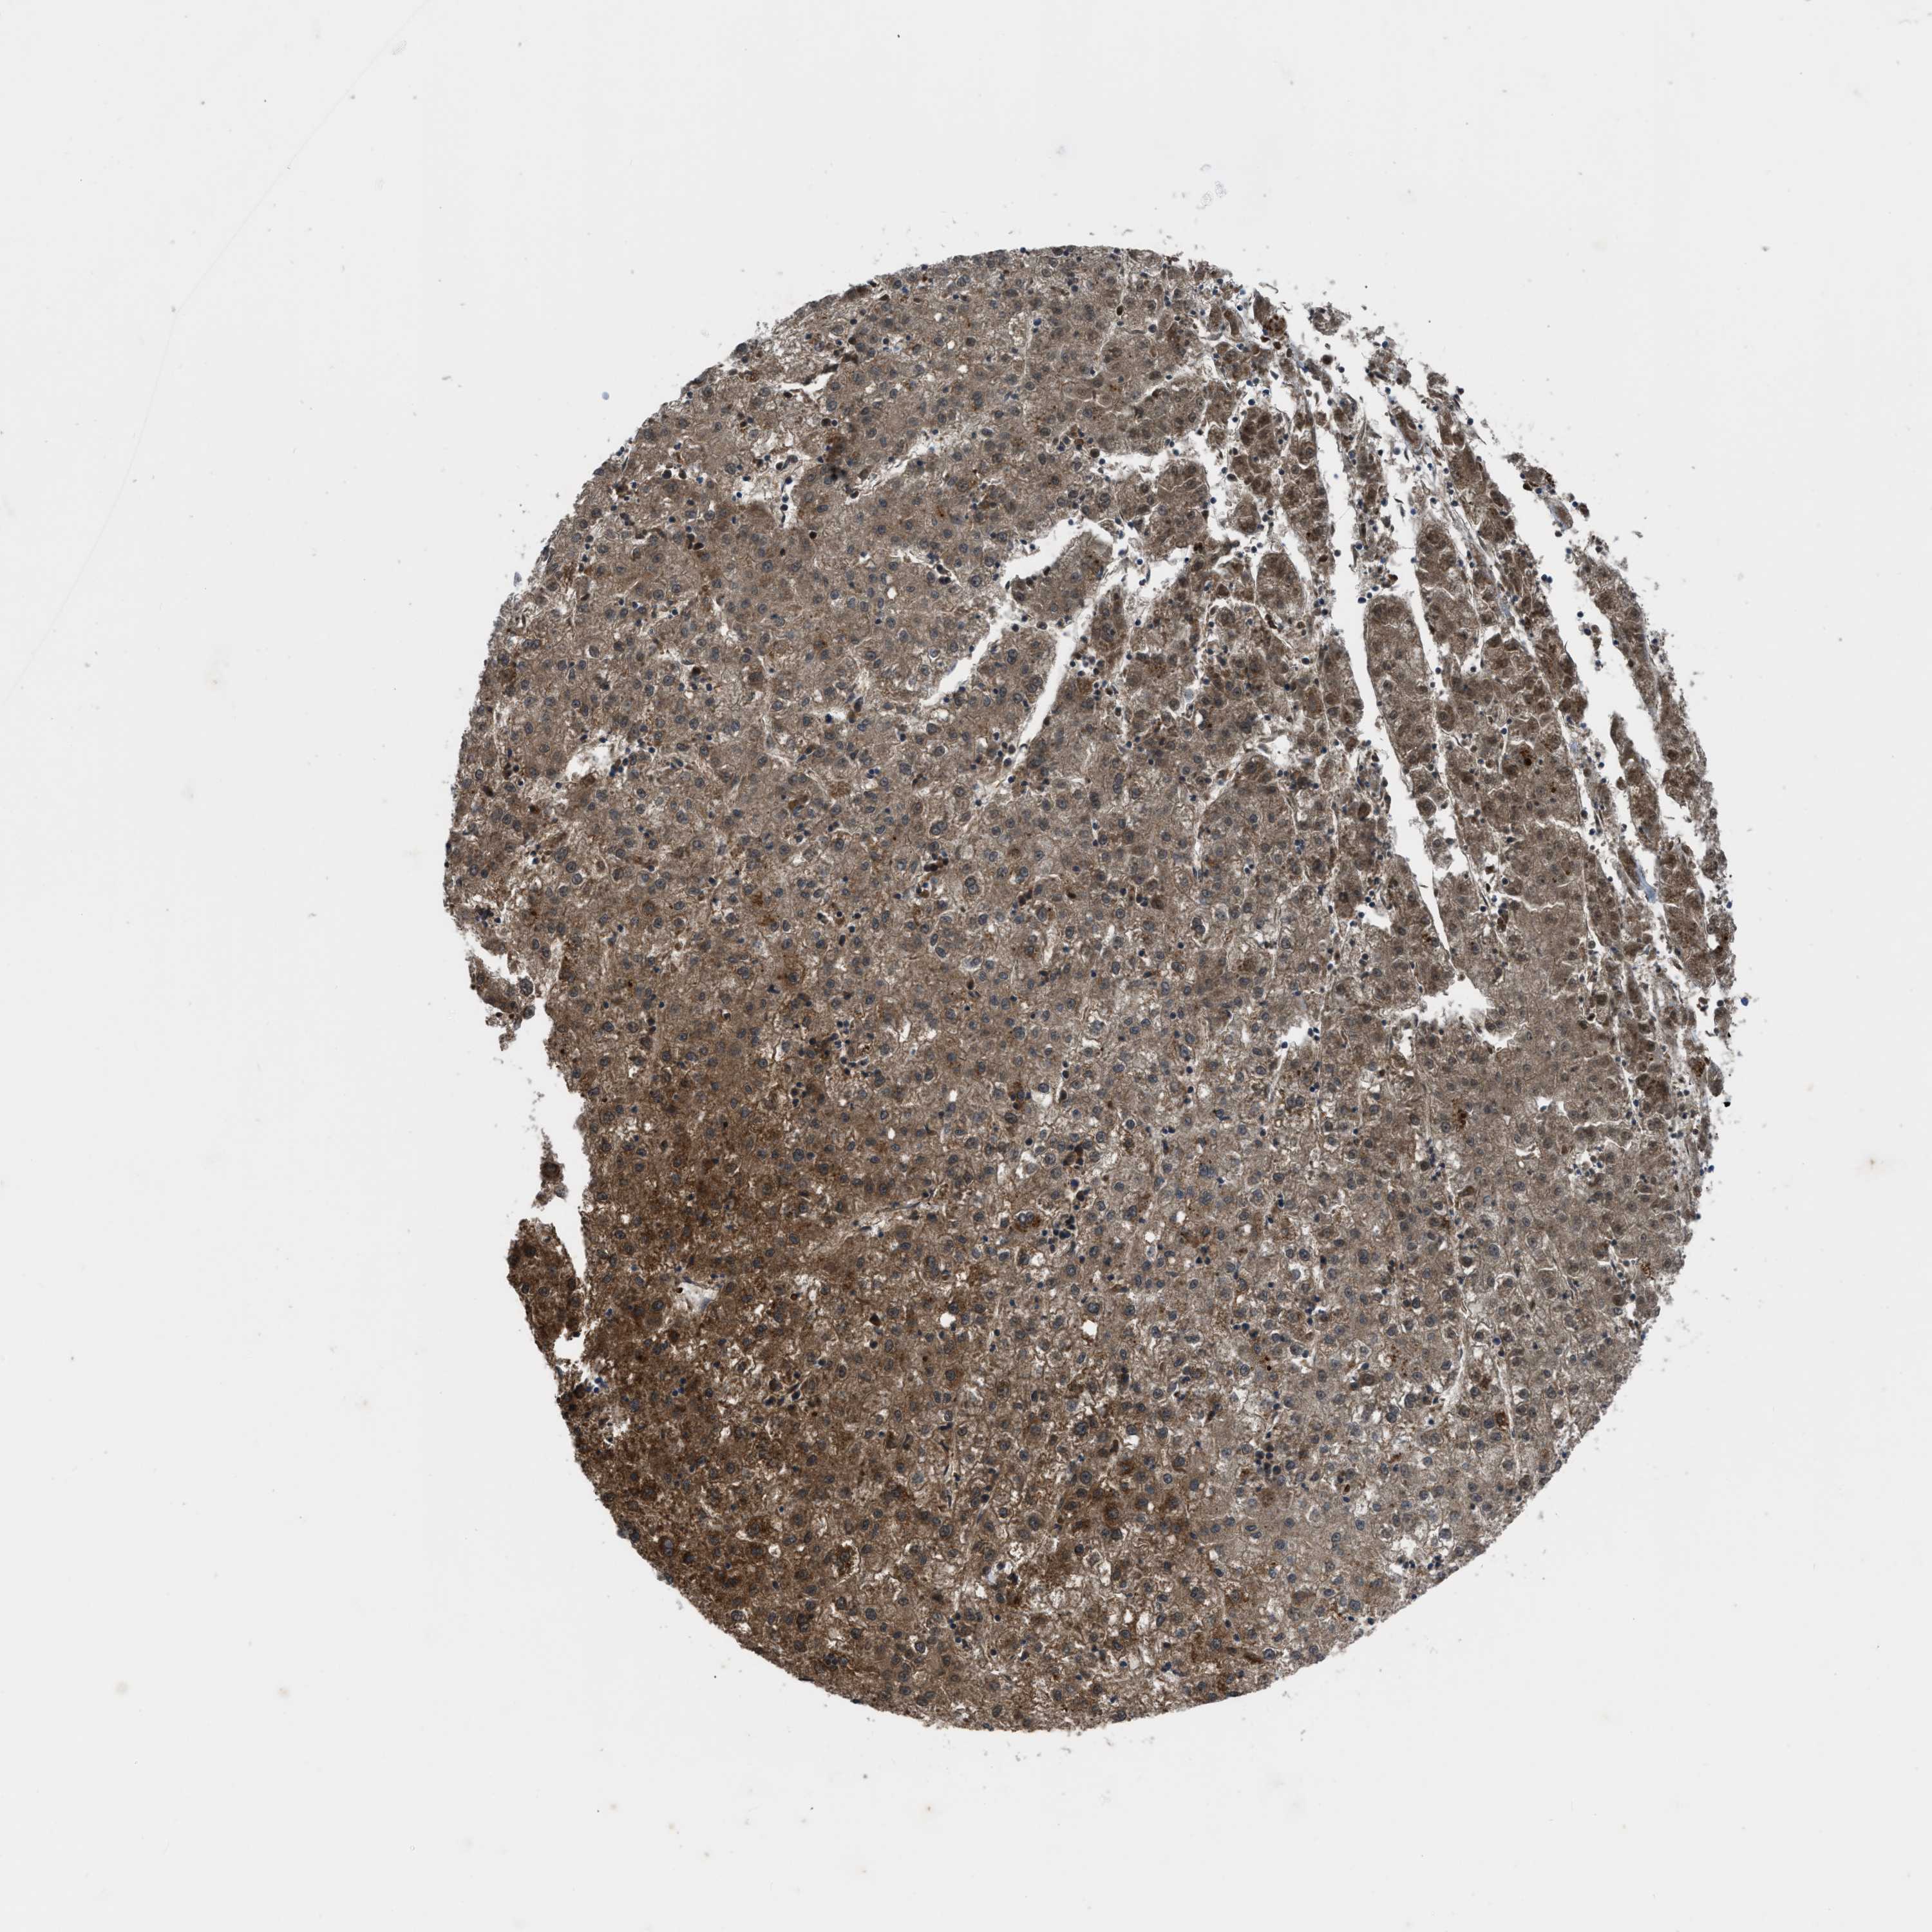

LIVER CANCER - Protein expressioni

A mouse-over function shows sample information and annotation data. Click on an image to view it in a full screen mode. Samples can be filtered based on level of antibody staining by selecting one or several of the following categories: high, medium, low and not detected. The assay and annotation is described here.

Note that samples used for immunohistochemistry by the Human Protein Atlas do not correspond to samples in the TCGA dataset.

Antibody stainingi

Antibody staining in the annotated cell types in the current human tissue is reported as not detected, low, medium, or high, based on conventional immunohistochemistry profiling in selected tissues. This score is based on the combination of the staining intensity and fraction of stained cells.

Each image is clickable and will lead to virtual microscopy that enables deeper exploration of all samples and also displays staining intensity scores, fraction scores and subcellular localization as well as patient and tissue information for each sample.

Antibody HPA018910

Antibody HPA018921

Antibody HPA018923

Staining

High

Medium

Low

Not detected

Intensity

Strong

Moderate

Weak

Negative

Quantity

>75%

75%-25%

<25%

None

Location

Nuclear

Cytoplasmic/membranous

Cytoplasmic/membranous,nuclear

Cholangiocarcinoma

Carcinoma, Hepatocellular, NOS